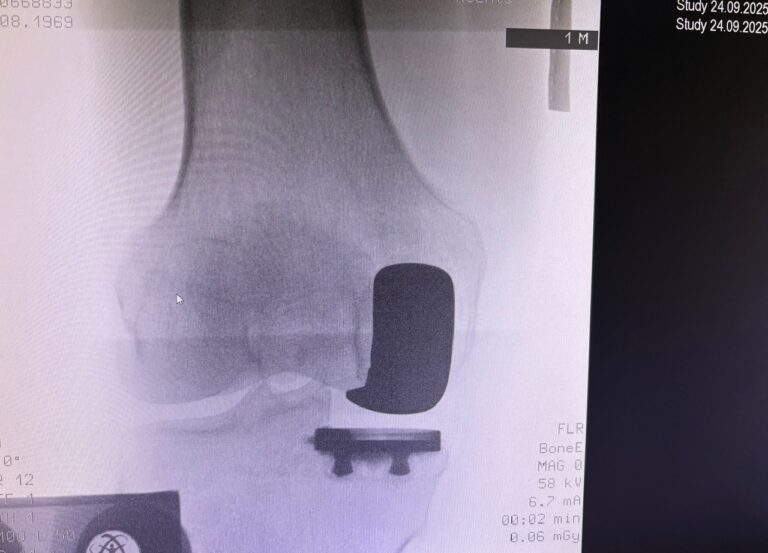

Η ημιολική αρθροπλαστική γόνατος (partial / unicompartmental knee replacement) είναι επέμβαση όπου αντικαθίσταται μόνο το φθαρμένο διαμέρισμα του γόνατος και όχι ολόκληρη η άρθρωση.

Πότε ενδείκνυται

- Οστεοαρθρίτιδα ενός μόνο διαμερίσματος:

- έσω (συχνότερα)

- έξω

- επιγονατιδομηριαίο

- Άθικτοι σύνδεσμοι (κυρίως πρόσθιος χιαστός)

- Καλή κινητικότητα γόνατος

- Σχετικά περιορισμένη παραμόρφωση

Πώς γίνεται

- Μικρότερη τομή από την ολική

- Αντικατάσταση μόνο του πάσχοντος διαμερίσματος

- Διάρκεια επέμβασης: ~1 ώρα